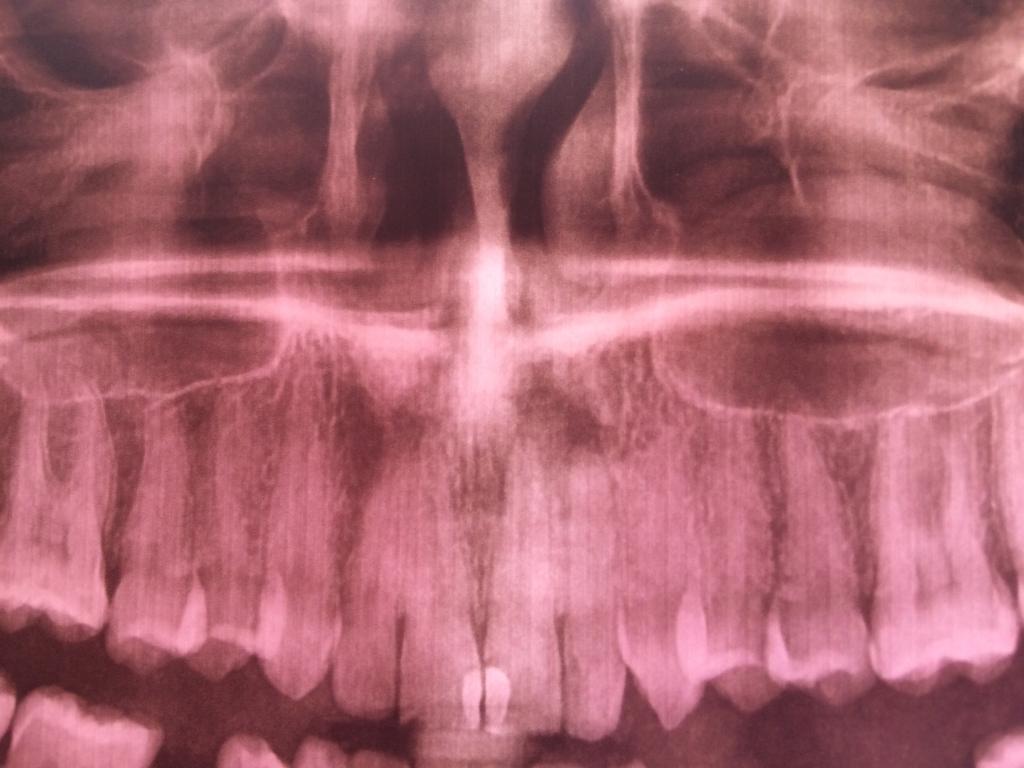

Здравствуйте, подскажите клинику с лазерным удалением кисты, или может ее можно вылечить? Была в клинике Дюна на посёлке Котовского, сделала снимок всей челюсти, они сказали что не знают что это, можно почистить каналы и посмотреть что будет. Сразу же прошла в стоматологическую клинику 5 , сказали что киста, нужно оперировать . Самое главное по какой причине обратилась к врачу это нарыв на десне, гной выдавливаю, пару дней спокойно, после снова набирает. Пожалуйста помогите, не хочу зубы терять.Нажмите на изображение для увеличения

Название: A0B3EA4C-5828-4AEF-A708-771D1F042B1B.jpg

Просмотров: 45

Размер:	73.0 Кб

ID:	12613665Нажмите на изображение для увеличения

Название: 1F2A227A-5E40-4FF0-91A3-15A2061A2B3D.jpg

Просмотров: 43

Размер:	40.3 Кб

ID:	12613666

Здравствуйте, подскажите клинику с лазерным удалением кисты, или может ее можно вылечить? Была в клинике Дюна на посёлке Котовского, сделала снимок всей челюсти, они сказали что не знают что это, можно почистить каналы и посмотреть что будет. Сразу же прошла в стоматологическую клинику 5 , сказали что киста, нужно оперировать . Самое главное по какой причине обратилась к врачу это нарыв на десне, гной выдавливаю, пару дней спокойно, после снова набирает. Пожалуйста помогите, не хочу зубы терять.Вложение 12613665Вложение 12613666

...пролечить зуб, запломбировать канал...возможно, и хирургия не понадобится...